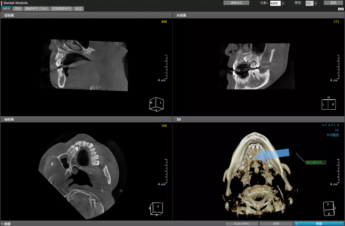

隐匿性口腔问题的探测神器——口腔CBCT

迷失自我的牙齿